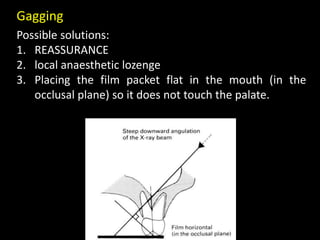

3. Special considerations for intra-oral radiography include techniques for mandibular third molars, gagging patients, endodontic procedures, edentulous ridges, and pediatric patients.